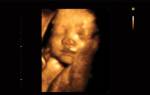

Внутриутробное развитие плода к 38 неделе беременности полностью завершается. Теперь малыш готов появиться на свет и самостоятельно существовать во внешнем мире. Его системы и органы сформированы.

Что касается малыша, к этому времени он набирает вес от 3-х и более килограмм, вырастает минимум на 47 см, расстается с первородной смазкой и лануго (тонким волосяным покровом тела). Его развитие закончилось, все внутренние органы сформированы. Легкие подготовлены к первому вздоху, сердечко – к кровеобеспечению организма.

Внешне и внутренне, малыш уже полностью сформирован, его вес может достигать 3 кг., при росте до 49-50 сантиметров. Ваш малыш ростом с лук-порей

Вес ребёнка на 38 неделе беременности уже может быть около 3000 г и более, а его рост – чуть больше 50 см.